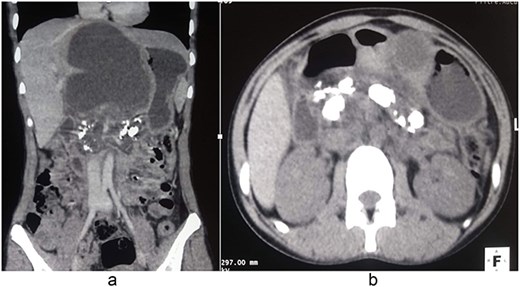

A 15-year-old girl was admitted with a painful epigastric mass associated with recurrent vomiting, evolving over two years. She reported repeated episodes of refractory abdominal pain and progressive weight loss, resulting in significant disruption of school attendance. There was no family history of pancreatic disease and no history of alcohol or drug use. Physical examination revealed a fixed, mildly tender epigastric mass measuring ~7 cm. Laboratory investigations showed microcytic hypochromic anemia (hemoglobin 7.2 g/dl) and a prothrombin rate of 78.9%. Renal function, serum electrolytes, fasting blood glucose, liver function tests, tumor markers (CA 19–9 and CEA), serum calcium, and triglyceride levels were within normal limits. Computed tomography revealed pancreatic macrocalcifications, marked dilation of the Wirsung duct, and a large pancreatic pseudocyst measuring 107 × 83 × 140 mm, with minimal intraperitoneal fluid (Fig. 1). These findings were consistent with CCP complicated by a pancreatic pseudocyst. After appropriate preoperative optimization, exploratory laparotomy was performed under general anesthesia. Intraoperative findings included a fibrotic, inflamed pancreas, a large interhepatogastric pseudocyst arising from the pancreatic body, and signs of segmental portal hypertension. Needle aspiration of the pancreatic parenchyma yielded a brown-colored pancreatic juice (Fig. 2). Longitudinal pancreatotomy centered on the dilated Wirsung duct revealed multiple intraductal calculi, which were extracted, followed by ductal irrigation (Fig. 2). A side-to-side pancreaticojejunostomy using a transmesocolic Roux-en-Y limb was performed (Fig. 3). Cholecystectomy, side-to-side choledochoduodenostomy, and cystogastrostomy with cavity drainage were also carried out. The postoperative course was uneventful. Oral feeding was started on postoperative day 5. Histopathological examination confirmed chronic pancreatitis with pancreatic pseudocyst. Long-term follow-up demonstrated complete pain relief, weight gain, and resumption of normal school activities.

Contrast-enhanced computed tomography showing CCP complicated by a large pancreatic pseudocyst. (a) Coronal reconstruction demonstrating a large pancreatic pseudocyst with associated pancreatic duct calcifications. (b) Axial image showing extensive intraductal pancreatic calcifications consistent with CCP.